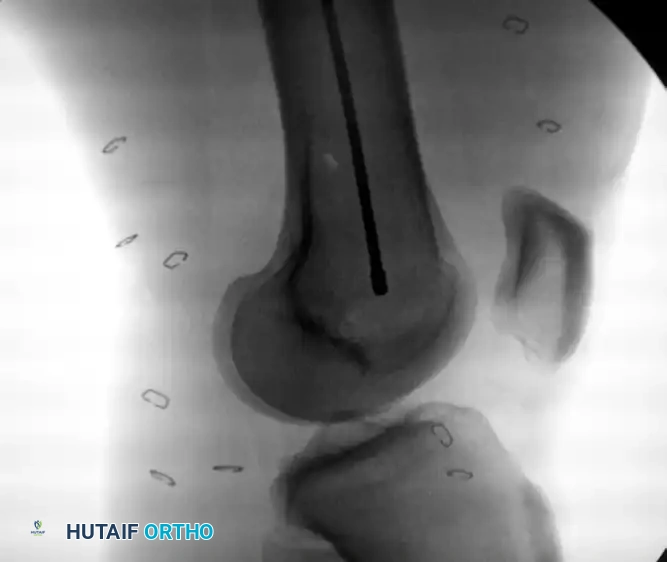

Confirm the reduction and the guidewire position with multiplanar fluoroscopy. The ultimate goal is concentric, central placement of the wire in the distal femur, terminating exactly at the level of the epiphyseal scar (or the midportion of the patella on an AP view).

Image

Intramedullary bead-tipped guidewire inserted concentrically to the distal femur at the level of the distal femoral physeal scar.